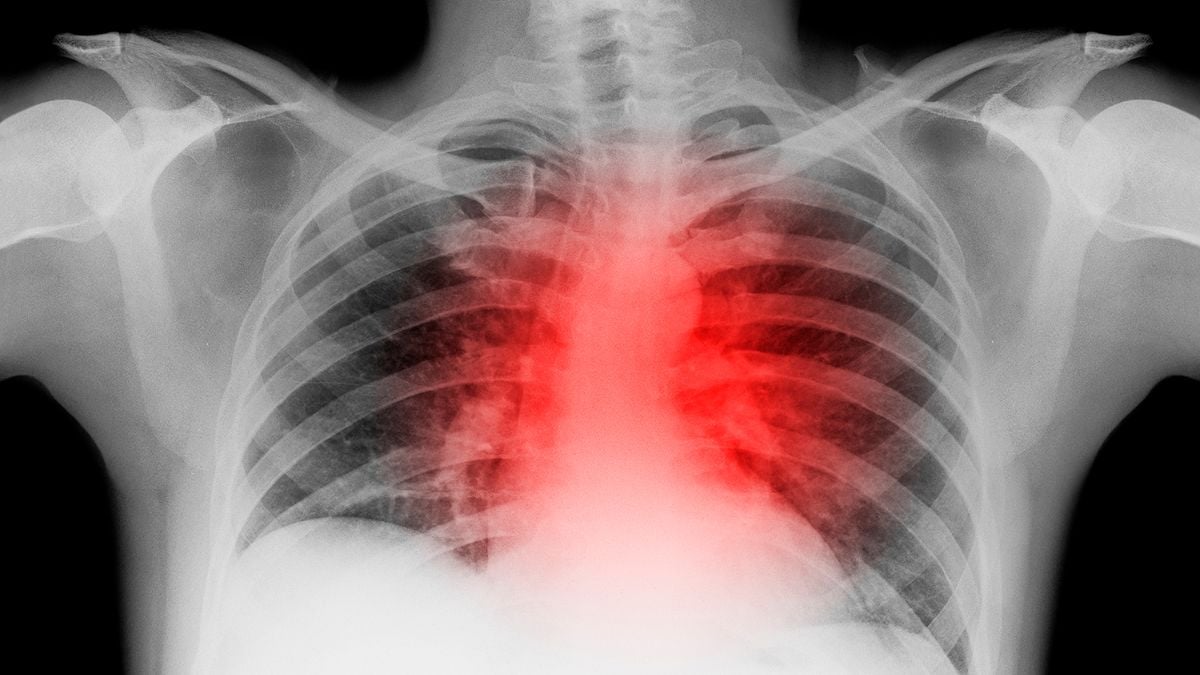

Las secuelas que deja la Covid-19 en el corazón: Inflamación y marcas como las de un infarto

La salud del corazón puede verse afectada, y con efectos duraderos, a consecuencia de la Covid-19, aunque esta puede pasar desapercibida a priori, una vez que el paciente se ha recuperado.

A todos ellos se le hicieron resonancias magnéticas de su corazón dos o tres meses después de que se les diagnosticara el virus, cuando muchos parecían haberse recuperado por completo. Las imágenes se compararon con personas que nunca habían tenido COVID-19 y algunas de ellas mostraban secuelas realmente increíbles.

De hecho, de esos 100 pacientes con Covid-19, 78 todavía tenían signos visuales de que el virus tenía un impacto en el corazón. En concreto, sesenta tenían signos de inflamación continua del músculo cardíaco.